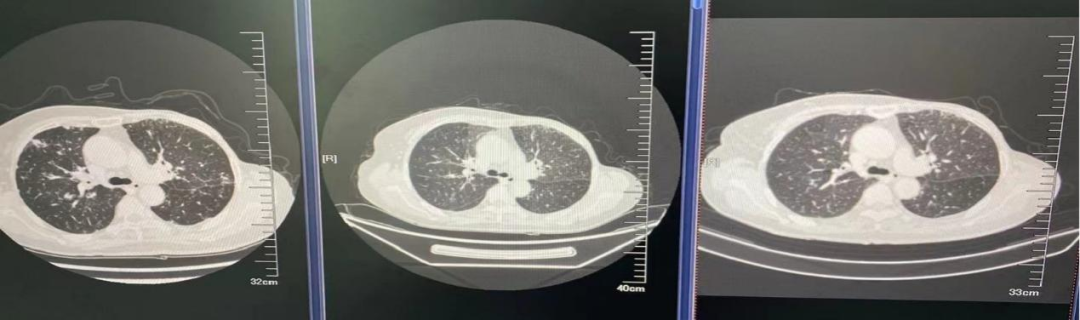

图4.肺窗

2021年4月7日双肺示:转移可能。

2021.04.05至荥阳市中医院查CT:1、左侧乳腺癌术后;2、双肺多发结节,转移可能,感染性病变待排;3、胸椎异常密度,转移可能;4、冠状动脉钙化;5、肝内多发低密度影。

2021.04.06至河南省肿瘤医院完善CT:双肺、肝、骨多发转移灶可能;ECT:全身多发骨质代谢异常,考虑多发骨转移。